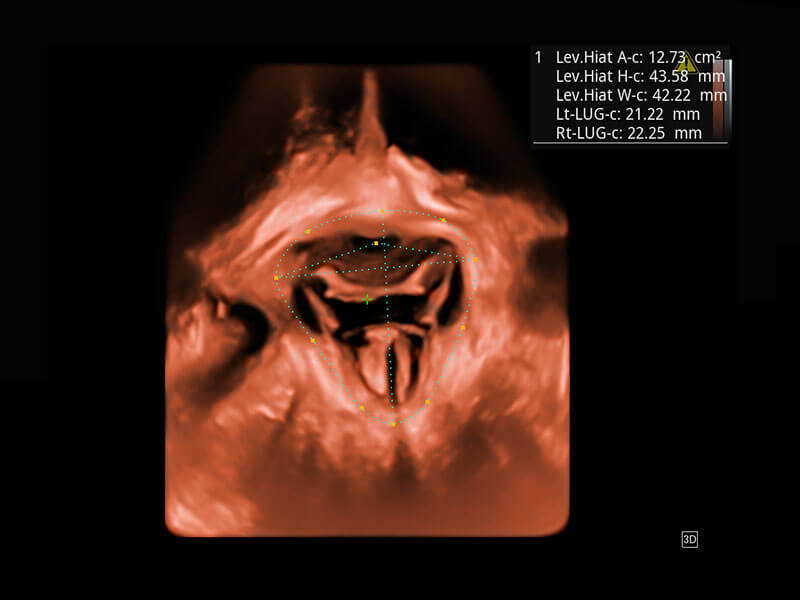

Lev.Hiat A-r: 16.33 cm2

Lev.Hiat H-r: 53.70 mm

Lev.Hiat W-r: 43.96 mm

Lt-LUG-r: 24.16 mm

Rt-LUG-r: 19.94 mm

S-Pelvic

能够简化盆底检查的操作流程,可在二维模式及三维成像模式下实现一键自动提取出标准切面、自动识别当前切面、自动测量,提升盆底检查的高效性,同时也能让青年医生快捷的获得准确的检查结果。